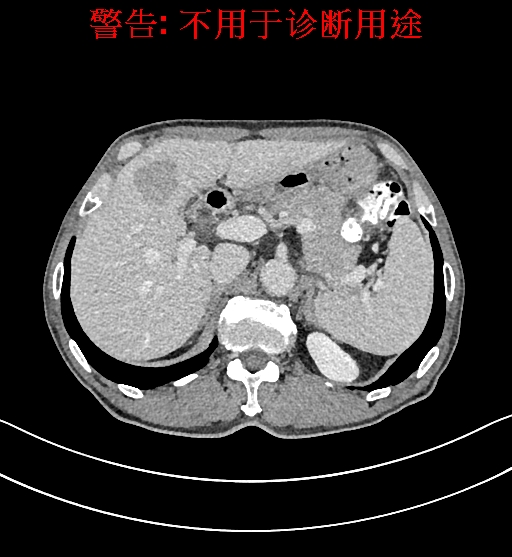

术前CT检查:

静脉期

上腹部动态CT扫描示肝左内叶占位,考虑肝Ca可能性大,请结合临床肝多发小囊肿。

通过调节窗宽窗位调整CT序号,对肿瘤,肝实质,胆囊,下腔静脉,肿瘤,肝动脉、门静脉及肝静脉等进行三维重建;系统自动计算肿瘤体积和肝脏体积。模拟手术操作,自动计算切除肿瘤体积。肝脏体积为1320ml,肿瘤体积为37.88ml,通过比对70-80岁正常肝脏体积为1263.13±170.25 ml,通过术前模拟手术,精准判断切除后剩余肝脏体积能耐受,避免肝衰竭发生。